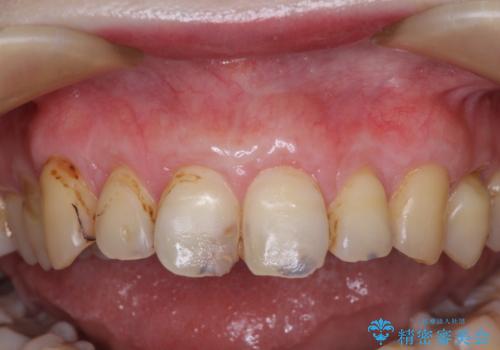

犬歯を中心に、露出量の多かった歯は十分に被覆することができました。

また、歯根のシルエットが見えた術前の状態と比較して、術後は歯肉が非常に厚くなっている状態となりました。